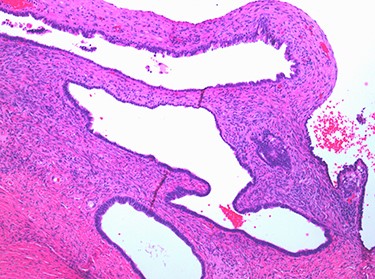

Despite the sinister appearance macroscopically, histopathology was benign. The ovaries contained multiple, benign, ciliated and epithelial cysts. Pelvic washings were negative for malignancy and the tubes were unremarkable.

Multiple cysts of variable diameter lined by a single layer of epithelium, separated by ovarian stroma; haematoxylin and eosin stain, medium magnification, scale ×10.

The case emphasizes the diagnostic importance of histopathology, particularly in the setting of unanticipated and sinister macroscopic findings. The macroscopic appearances of the ovaries suggested malignancy diagnosis; however, the histopathology identified benign epithelial cysts [15]. The cyst lining was comprised of a single layer of epithelial cells amid normal ovarian stroma (Figs 6 and 7). The cysts contained normal serous epithelium with cilia lining the cyst lumen. These histological findings are consistent with the Müllerian phenotype and are therefore endosalpingiosis, ectopic tubal cell deposits on the surface of the ovaries, not that of hydrosalpinges or malignant ovarian cysts as the diagnostic rollercoaster suggested [15].

Normal serous epithelium with prominent delicate cilia lining the cyst lumen; haematoxylin and eosin stain, high magnification, scale ×40.